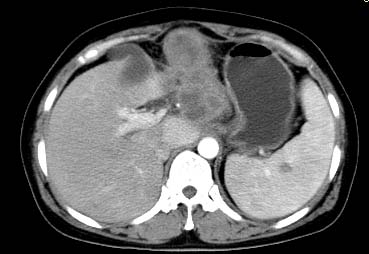

以下是引用西北一只狼在2008-6-30 20:58:00的发言:[br]肝左叶胆管细胞ca并肝门淋巴结转移、胰腺、胃小弯浸润

以下是引用ydx_74在2008-6-30 21:54:00的发言:[br]左叶胆管细胞ca并肝门淋巴结转移、胰腺、胃小弯浸润